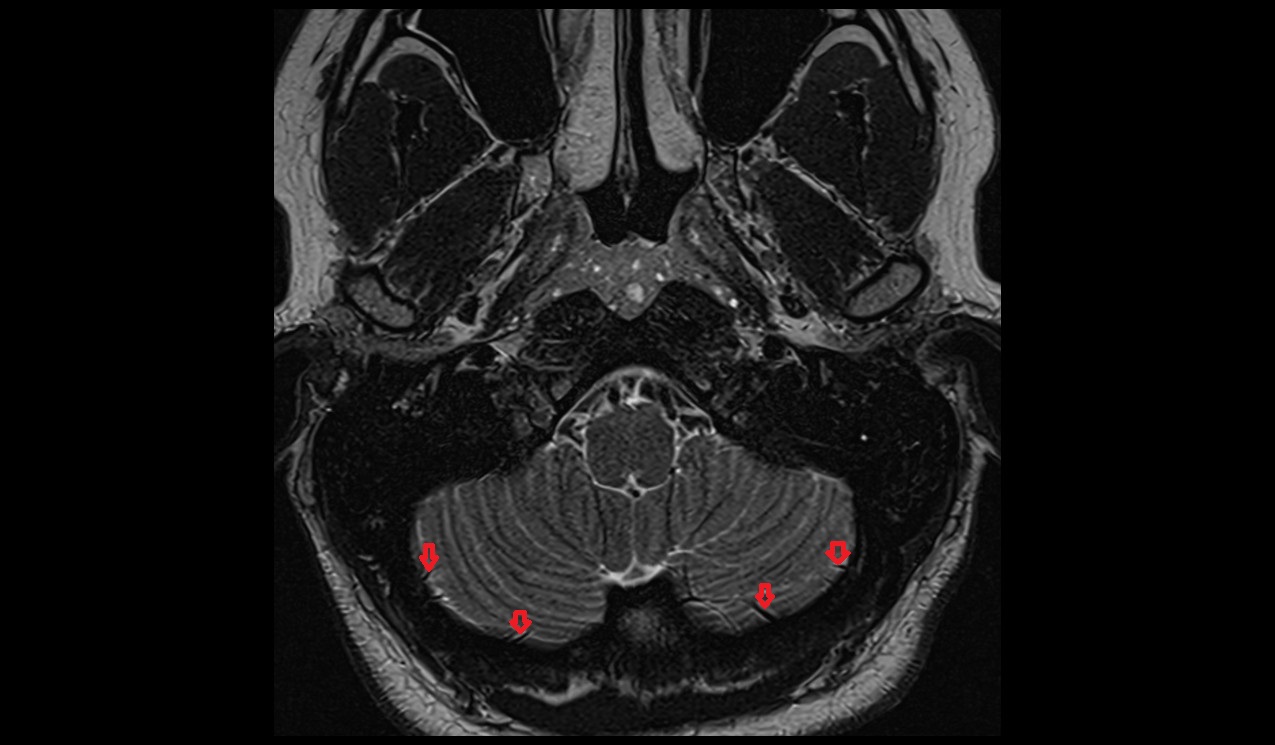

- Crus I of ansiform lobule of cerebellum

- Crus II of ansiform lobule of cerebellum

- Paramedian lobule (HVII) of cerebellum

- Simple lobule (HVI) of cerebellum

- Anterior quadrangular lobule (HV) of cerebellum

- Anterior quadrangular lobule (HlV) of cerebellum

- Biventral lobule (HVIII) of cerebellum

- Cerebellar tonsil (H IX)